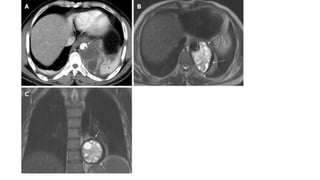

• A 48-year old male with mediastinal hydatid cyst presented with acute

chest pain. A: Axial image of enhanced computed tomography

angiogram shows a complex cystic lesion with thick wall (white arrows)

that is predominately located in the left side of the posterior

mediastinum with evidence small calcifications at the periphery of the

lesions at the site of abutment with descending thoracic aorta. There is

adjacent pleural effusion (white asterisk) and enhancing left lower lobe

atelectasis (white asterisk); B, C: Axial and coronal T2 weighted images

show a complex cystic lesion with thick dark rim (arrows) abutting the

descending thoracic aorta with multiple peripheral daughter cysts of

higher signal intensity compared to the intermediately hyperintenese

matrix of the mother cyst. Magnetic resonance imaging findings are

highly suggestive of hydatid cyst, likely primary given absence of

evidence of lung and liver hydatid disease.